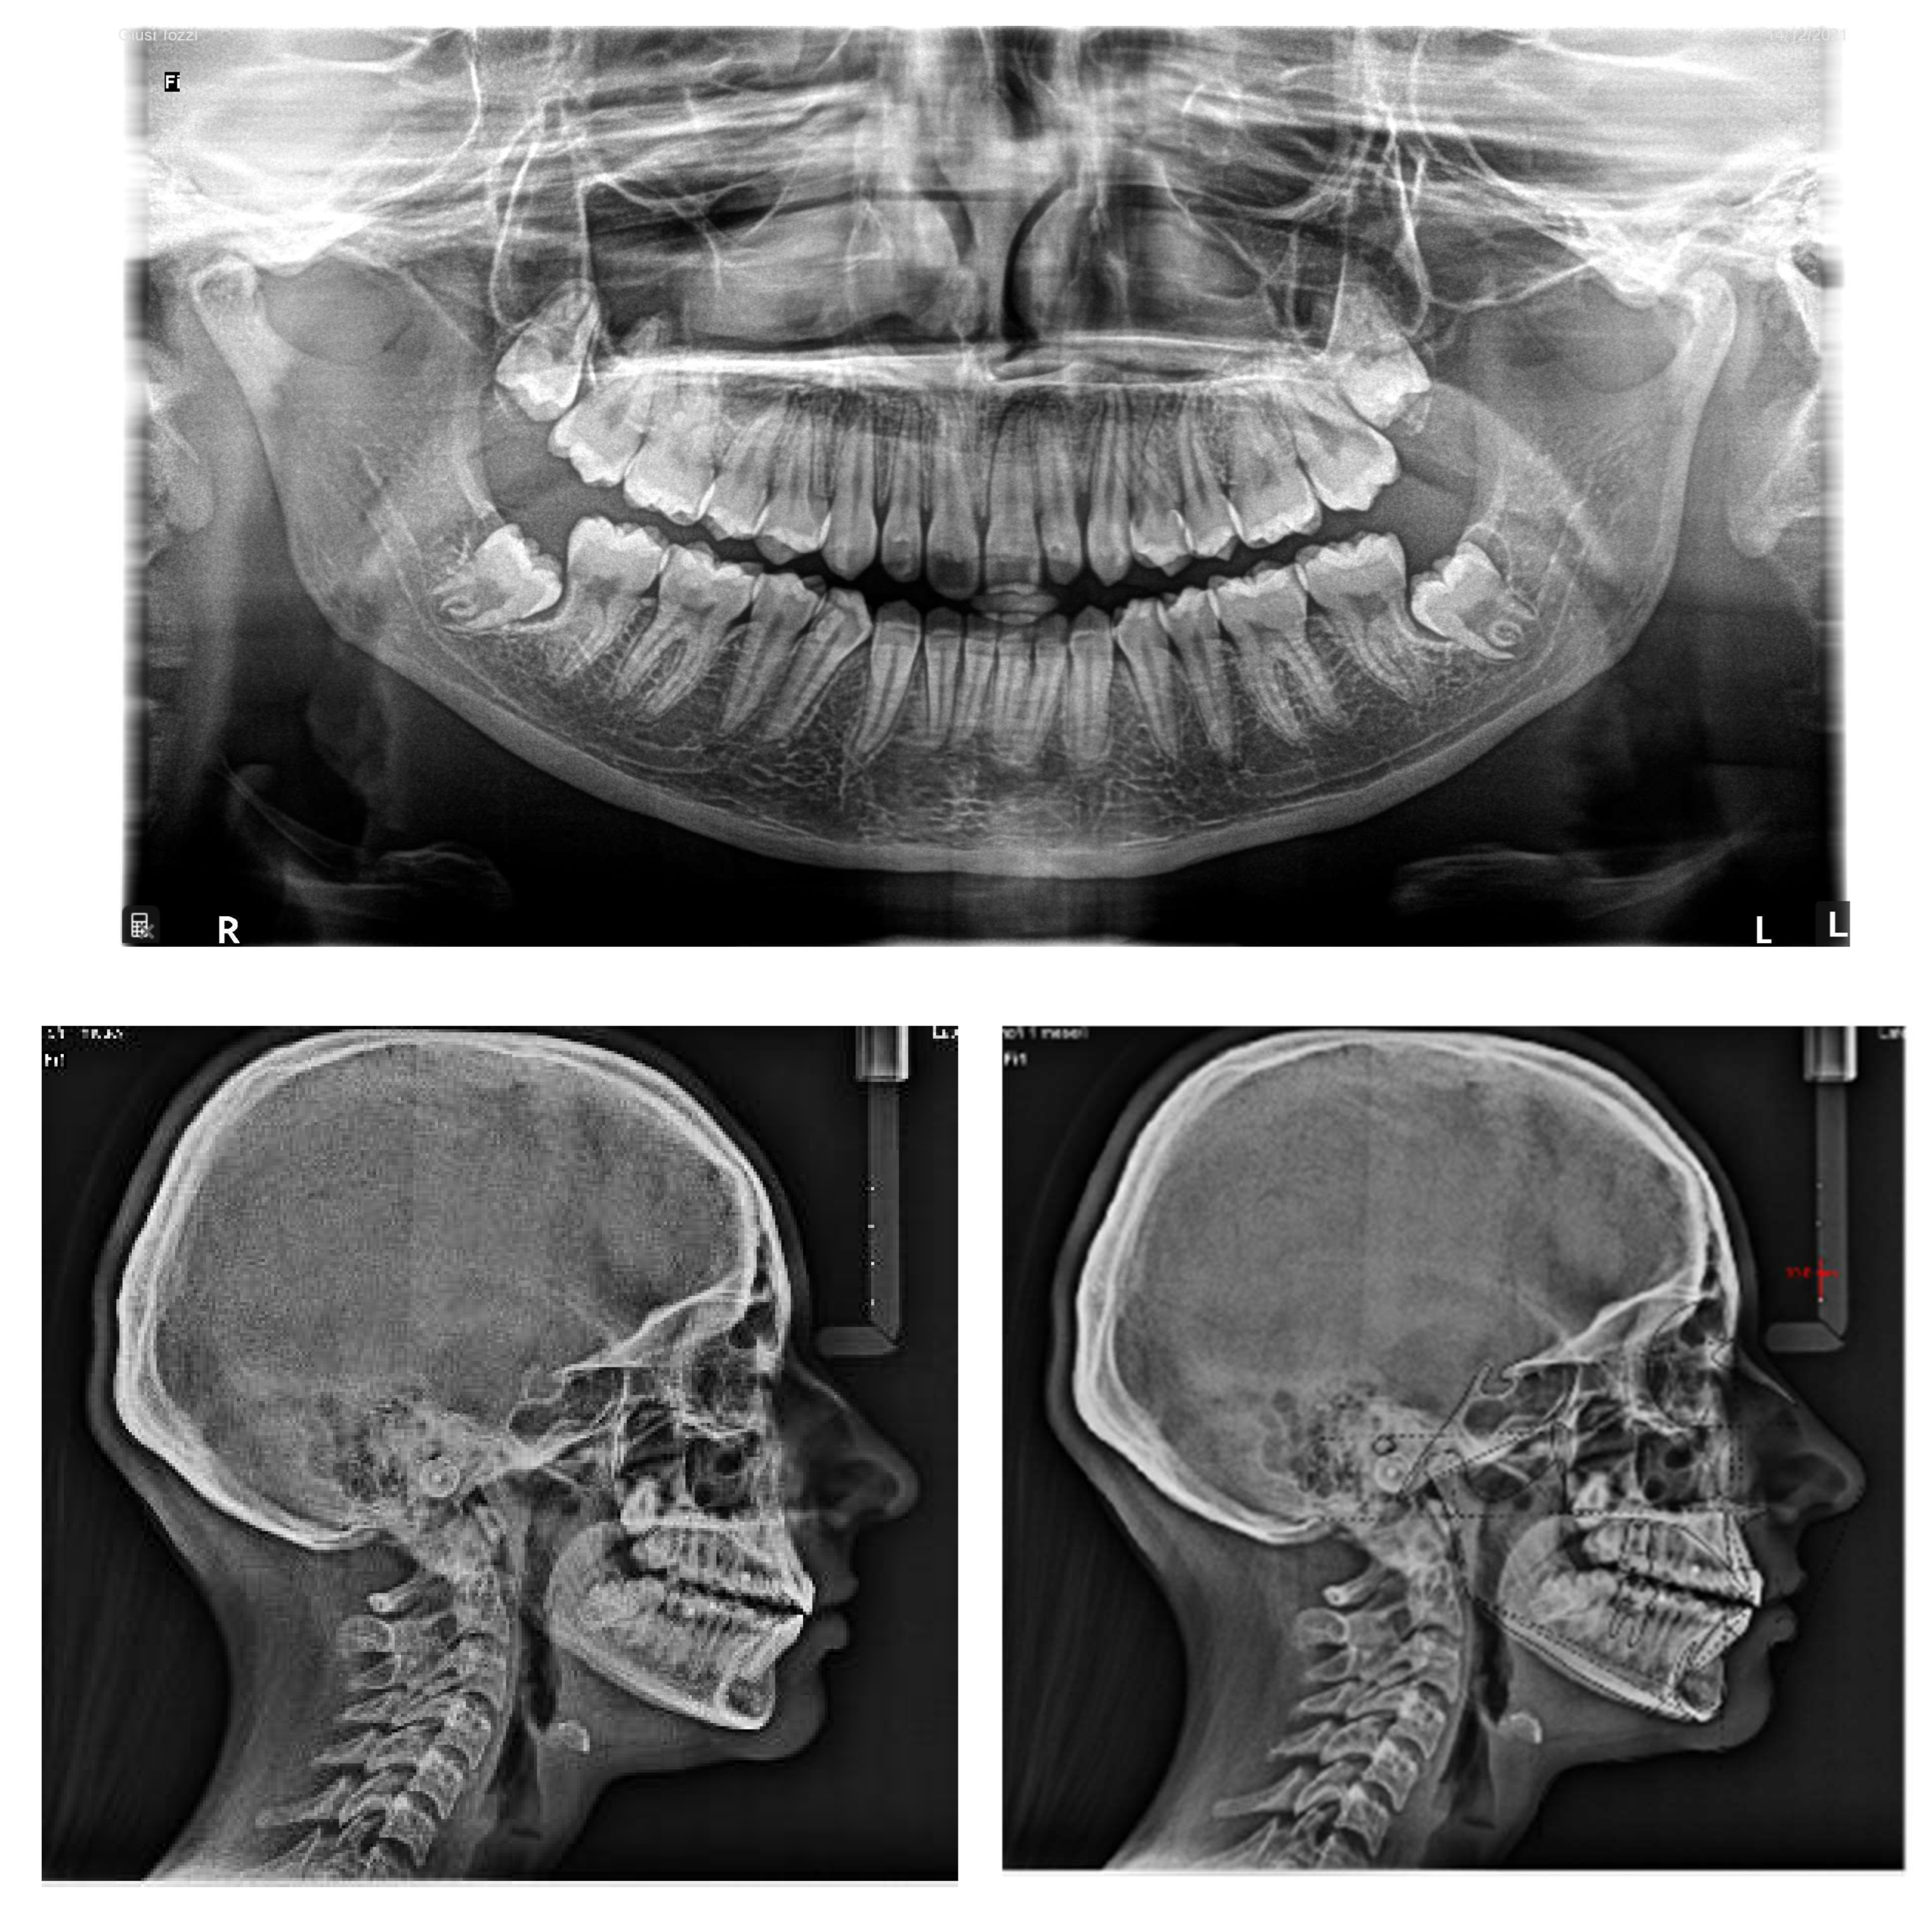

From a lateral view, the profile appeared straight and a normal nasolabial angle, labiomental sulcus, and lip competence was represented. The initial records were collected and X-rays were taken (Figure 1).

Figure 1.

A 17-year-old female with dentoskeletal Class I with an impacted upper right canine before treatment.

Intraorally, the patient had Class I molar and canine relation on both sides, along with normal overbite, overjet, and the retention of the deciduous canine.

The cephalometric analysis showed a skeletal Class I (ANPg +1.7°) with a good proportion of the maxillaries (SNA 84°; SNB 82.3°) in a normo-divergent vertical pattern (SN^Go-Gn = 32.8°) and a good inclination of the upper and lower teeth, respectively (I/ANS-PNS 116.2°; i/GoGn 91.6°) (Table 1).

The panoramic X-ray showed unilateral permanent canine displacement in sector four with an alpha angle of more than 53° degrees according to the Ericson and Kurol classification (Figure 2).

Figure 2.

Pre-treatment panoramic X-ray with the evaluation of alpha angle and sector according to the Ericson and Kurol classification.